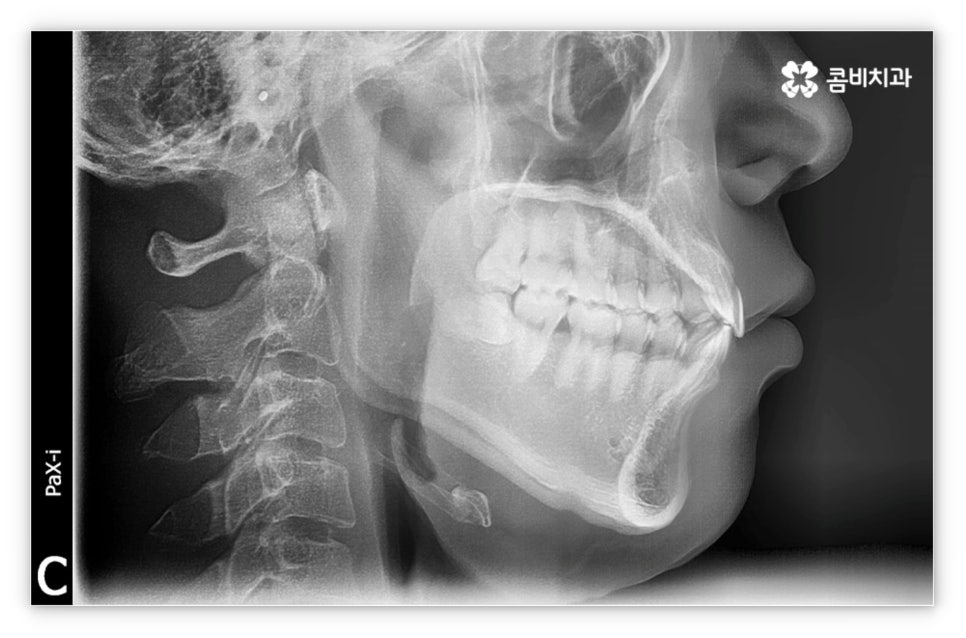

그리고 교정 치료는 그 목적상 위아래 교합이 똑바로 맞아 저작 기능을 제대로 수행할 수 있도록 하면서 가지런한 치열을 통해 발란스를 잡아주고 심미적으로도 좀 더 보기 좋은 안모를 형성하도록 하는 과정이기 때문에 환자의 치열과 교합, 얼굴 형태, 턱 관절 및 골격 구조 등 모든 부분을 세밀하게 파악하고 종합적으로 고려하여 각자에게 딱 맞는 교정 플랜을 세울 수 있도록 3D CT 와 같은 정밀 검진 기계를 갖추고 있는 치과에서 치료 받으시길 권유드리고 있는데요. 3D CT 는 일반 CT와 다르게 다각도에서 촬영을 하므로 환자분의 치아 위치, 턱관절, 얼굴의 정면 및 측면 등 다양한 정보를 수집하여 의료진 분들의 세밀한 파악을 돕는다는 장점이 있어요.

살펴본 바와 같이 앞니설측교정 의 장점에도 불구하고 아랫니 부분은 장치가 혀에 닿게 되기 때문에 환자분들께서 불편함을 느낄 수 있고 혹시라도 혀가 브라켓에 잘못 쓸리거나 눌렸을 때 통증이 발생할 수도 있으며 발음이 불분명해지는 문제가 생길 수 있는데요. 이러한 이유로 앞니설측교정 에 대해서 고민이 되시는 분들은 윗니 부분은 설측으로, 아랫니 부분은 일반 교정처럼 순측으로 진행하는 콤비 교정에 대해서 알아보시면 좋을 거예요. 위의 사진에서 살펴보실 수 있는 경우가 바로 이렇게 콤비 교정으로 진행한 환자분의 케이스인데 아랫니의 경우 보통 입술에 가려 별로 드러나지 않는 데다가 치아 색상인 세라믹 재질로 된 브라켓을 이용하기 때문에 설측 교정과 비교해도 심미성이 크게 떨어지지 않는다는 것을 알 수 있어요. 콤비 교정의 경우 설측 교정보다 비용적인 부담도 줄일 수 있으니 각 장치에 대한 장단점을 의료진분들과 충분히 상담하셔서 자신에게 맞는 장치를 선택하시면 좋을 거예요.